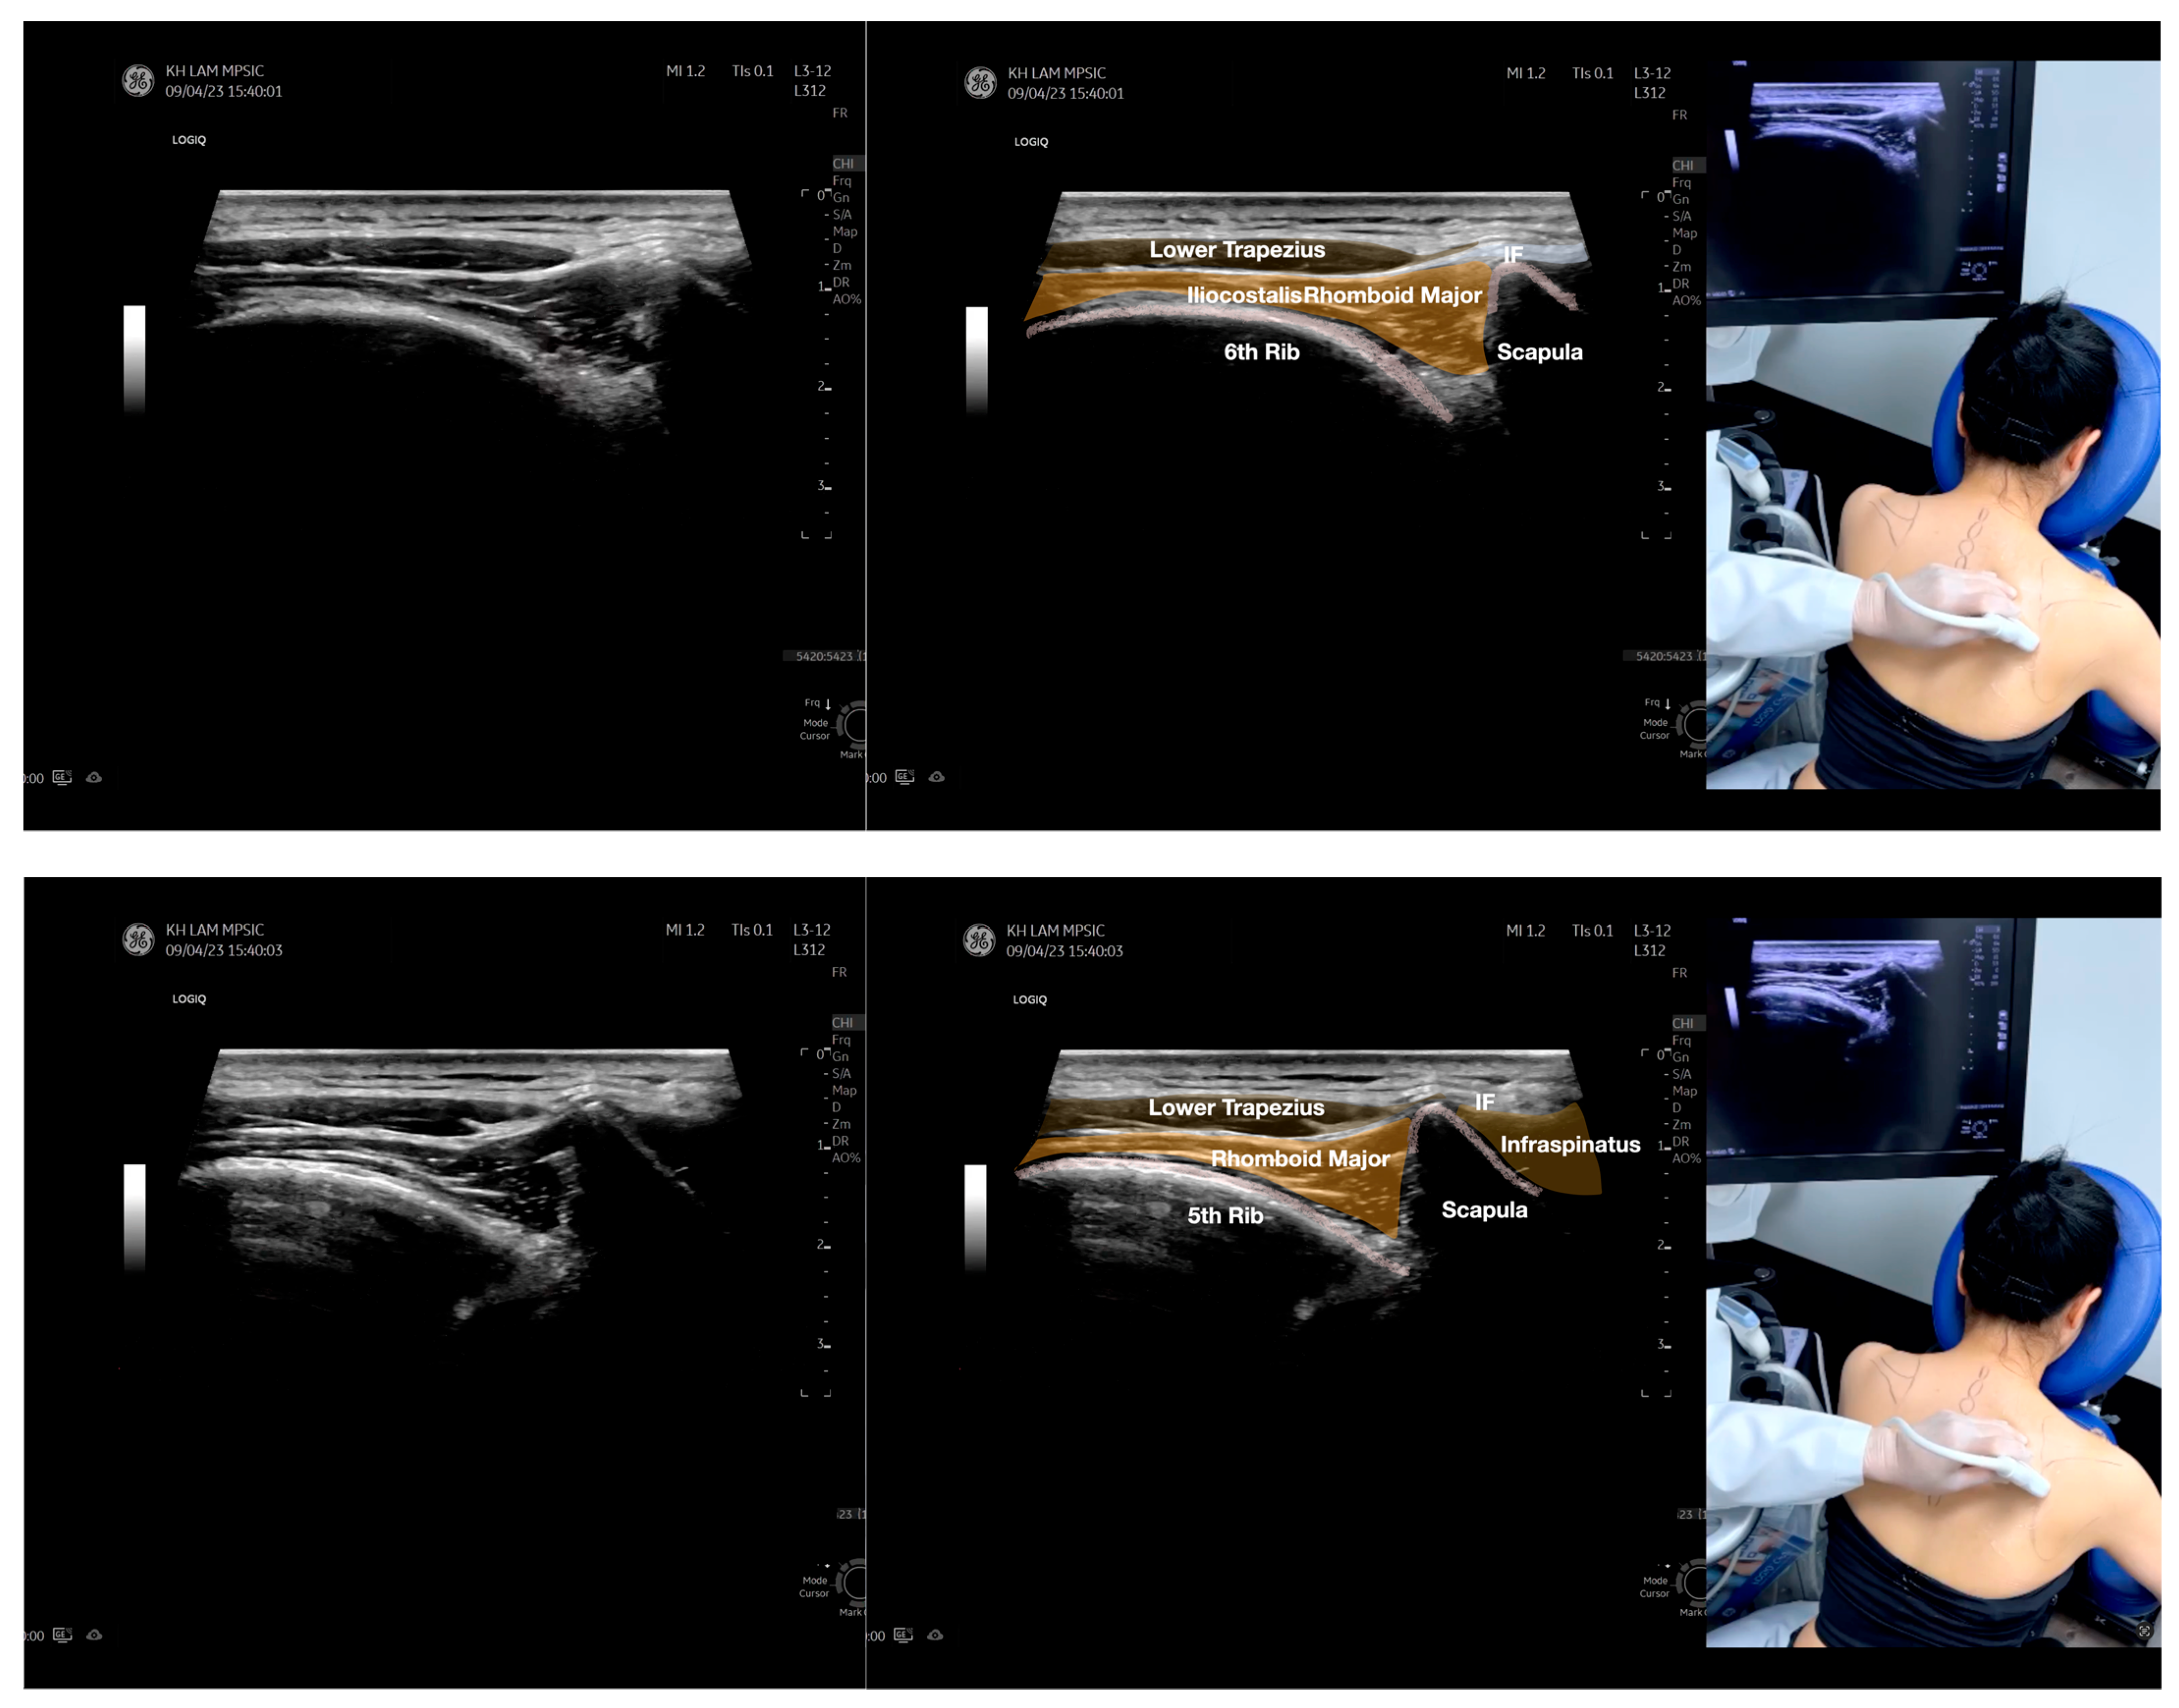

Figure 2.

Sonoanatomy of the lateral border of the inferior trapezius, its related muscles, and the infraspinatus fascia. The step-by-step scanning techniques of the structures illustrated in this figure have been shown in Video S6. Available online: https://www.dropbox.com/s/vjj49wiwdsidouz/Figure%202.docx?dl=0 (accessed on 1 January 2023). Dynamic ultrasound scanning of the anterior shoulder with the humerus externally rotated (palm up), elbow straight, and the shoulder actively flexed and abducted at about 90 to 100 degrees shows that the fibrotic and thickened bursa was noted to be snapping between the subscapularis tendon and the coracoacromial ligament, as shown in Video S3. The patient noticed this snapping during many of his daily activities with his shoulder flexed just above 90 degrees, e.g., taking off clothes and combing hair. Ultrasound-guided injection of the thickened and fibrotic bursa did not reproduce the usual pain nor reduce the pain, and it did not improve the shoulder snapping and flexion power with the elbow straight, shoulder flexed to 90°, and the humerus externally rotated (palm up). Ultrasound-guided injection of the cortical break reproduced the concordant pain and temporarily and partially reduced the pain with snapping and residual anterior shoulder pain (Video S4), but it did not change the snapping or weakness in the right shoulder flexion with the humerus in external rotation. With the failure of direct anterior treatment to the suspected lesions, it was essential to further explore other causes for the anterior painful snapping. Further detailed musculoskeletal examination of the scapular movement showed that the right scapulothoracic movements were not smooth compared to the left counterpart (Video S5) [4,5]. There might be some disruptions in the right infraspinatus fascia (IF) and its related muscles, including the lateral edge of the right inferior trapezius, rhomboid minor and major [6], teres major, latissimus dorsi [7,8] (LD), and posterior deltoid attachments to the IF [9,10]. Clinically, prominent and active trigger points were observed in the right infraspinatus muscle. Holding the inferior angle of the scapula, with the examiner’s fingers, especially over the origin of the teres major muscle over the scapula, the latissimus dorsi [11,12,13] and the scapular insertion of the rhomboid major muscle significantly improved the power of the resisted shoulder flexion with the elbow straight and the shoulder flexed to 90° with the humerus externally rotated (palm up). In order to illustrate the utilization of ultrasound-guided sonopalpation and ultrasound-guided digital palpation for detecting the suspected lesions of the IF and its related muscles, we presented the following videos (Videos S6–S9) and still images (Figure 2, Figure 3, Figure 4 and Figure 5) to demonstrate the essential techniques and crucial points of getting the normal sonoanatomy of the IF and its related structures. The gross anatomy of the IF and its related muscles were also shown in Figure 6, Figure 7 and Figure 8.